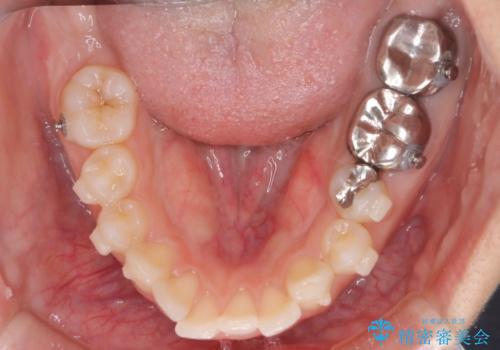

- 前歯が出ていることを主訴に来院された患者様です。

抜歯を希望されなかっため、臼歯部の遠心移動やIPRを行い配列を行っています。

抜歯をしていない矯正となるため、口元に大きな変化は認められません。